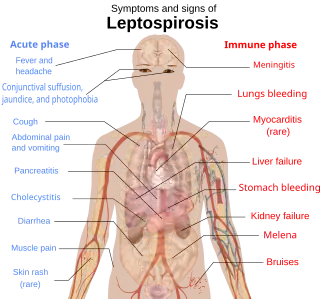

This article aims to provide a comprehensive overview of the infectious zoonotic disease Leptospirosis in tropical countries. Warm blooded animals such as mice, dogs, and cows can be infected by this disease and carry the disease to humans. Although cold blooded animals such as reptiles may have Leptospira bacteria in them, their role in causing diseases in humans are unknown. Once infected, symptoms can range from mild disease to life-threatening ones. The pathogenesis of the leptospirosis infection is not completely understood. Therefore, more researches are required to understand the disease. Searches into PubMed and Google Scholar were done by using keywords "leptospirosis", "human leptospirosis", "animal leptospirosis", "Leptospira", and "leptospirosis review" while writing this article. In conclusion, leptospirosis is a common disease in the tropics and the public should know the effective ways of avoiding or treating the disease.